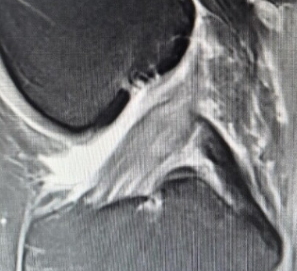

Ich war beim MRT ( Knie verletzt im letzten Skiurlaub), da nach 2 Monaten meine Knieprobleme nicht besser wurden. Ich war neugierig und hab die CD in meinen PC geschoben, hier ein Screenshot von einer Stelle, die glaube ich nicht so gut aussieht....

meinst du das?

Ich bin kein Arzt, also nimm meine Einschätzung bitte nicht als 100 % korrekt oder besser gar nicht Ernst.... Aber ich vermute, dass du ein Problem mit einem Kreuzbandriss hast...

Die Bänder sollten wie dicke, durchgehende schwarze Linien aussehen. Dein PCL scheint in Ordnung zu sein, aber dein ACL sieht nicht so gut aus.

Ich wiederhole: Ich bin kein Arzt, aber so sah das Bild meiner Frau aus, und der Arzt hat es damals bestätigt.

Zunächst fällt auf, dass viel "weiße Masse" auf dem Bild zu erkennen ist - und das an Stellen, wo sie nicht zwangsläufig sein sollte. Das lässt die Vermutung von Flüssigkeitsansammlung und damit Verletzungen innerhalb des Knies zu. Wenn ich das Bild mit jenem einer guten Freundin vergleiche, die sich im Dezember das Vordere Kreuzband gerissen hat, würde ich auch stark auf eine Verletzung des vorderen Kreuzbands tippen. Ob Teil- oder Komplettruptur, dafür reicht mein Laienwissen wahrlich nicht aus.